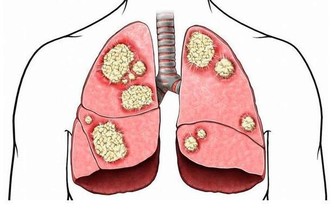

①不要抽煙。長期抽煙會導致肺癌、口腔癌、喉癌、食管癌等,同時還會增加患胃癌、肝癌等癌症的風險。